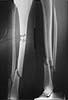

We have done the 2nd Fixion inflatable nail last Tuesday, for a 1st degree open distal tibial fracture. It was a 15 minute procedure and the patient walked next day out of the ward. The first patient had a eventful rehabilitation and was walking without crutches after one month (he was a polio patient on the operated limb). I am sending some pictures. Please note the hourglass shape of the inflated nail. I will keep the list informed of the follow up of those patients.